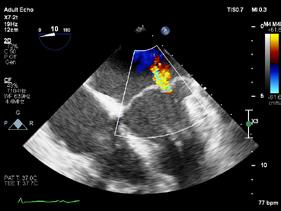

Cazuri disperate în chirurgia cardiacă –atunci când abordul minim invaziv este soluția

Dr. Ion Iovu, Prof. Univ. Dr. Lucian Dorobanțu, Dr. Andreea Bogdan, Dr. Ioana Băjenaru, Dr. Oana Ioniță, Dr. Mădălina Cojocaru, Dr. Toma Iosifescu, Conf. Dr. Cătălin Badiu, Dr. Alexandru Vasilescu